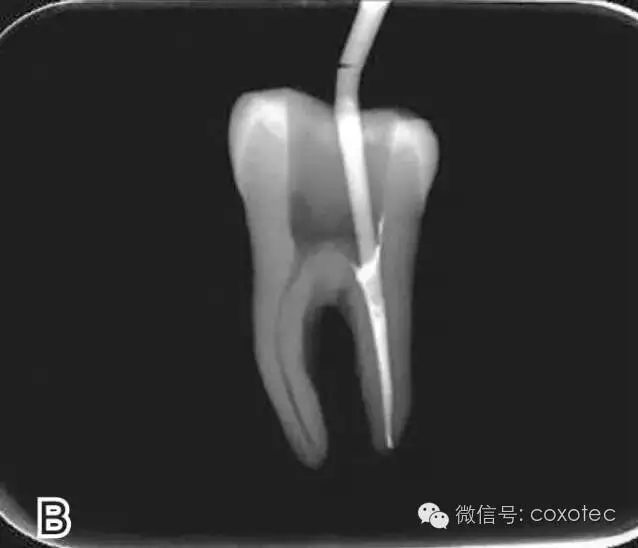

開(kāi)啟加熱器1秒鐘,迅速退出攜熱器工作尖,帶出中上段多余牙膠尖。用小號(hào)垂直加壓器向下加壓,完成根尖段的充填(圖7)。

圖7 退出攜熱器工作尖,A.垂直加壓器加壓 B.根尖段的充填完成